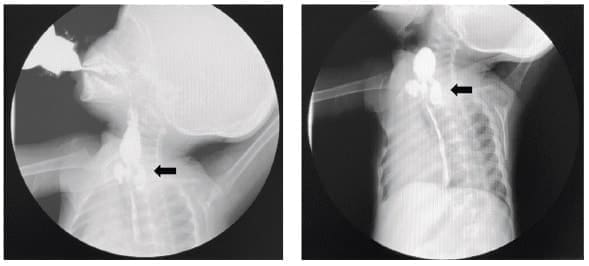

Posteriormente por la persistencia de la sintomatología, se realizó un esofagograma que identificó un divertículo faringoesofágico izquierdo, con una extensión de tres cm desde T1 a T2-T3 (Figura 1), con paso de medio de contraste al esófago.

Figura 1. Esofagograma en el que se observa un divertículo faringoesofágico a nivel de T1, con paso de medio de contraste al esófago y hacia el divertículo a la izquierda (flecha), con una extensión de 3 cm desde T1 a T2-T3.